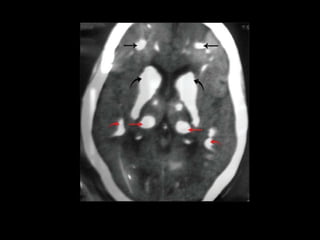

• Papilledema and calcification of the basal ganglia are other

signs of chronic hypocalcaemia.

Chronic hypoparathyroidism

• hypocalcemia ,Hyperphosphatemia with a low

parathyroid hormone(PTH) level is diagnostic.